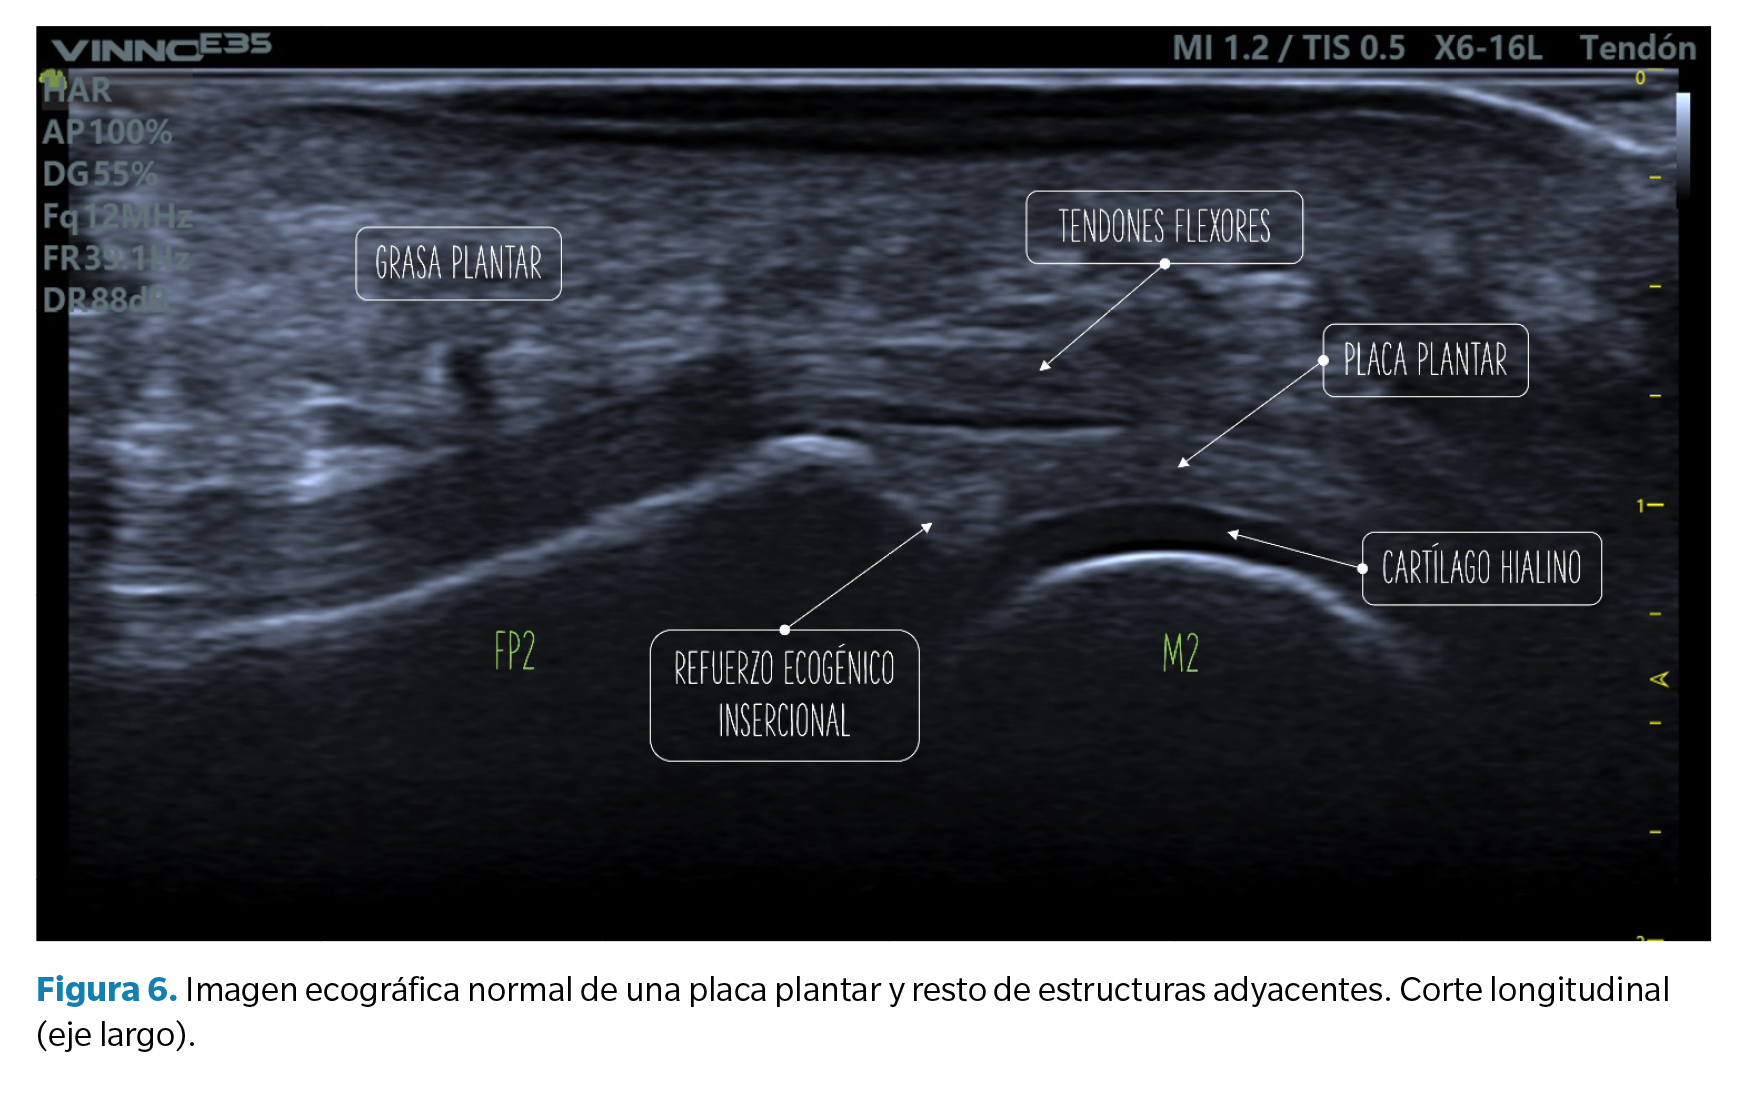

Criterios de normalidad de la imagen ecográfica

• Corte longitudinal (eje largo): la placa plantar normal se muestra ecográficamente como una estructura curvilínea ligeramente ecogénica con ecotextura granulada homogénea. Esta textura permite la diferenciación, no siempre definida, con los tendones flexores subyacentes de textura fibrilar. La superficie articular de la placa se define con precisión limitando con el cartílago hialino de la cabeza metatarsal, hipoecoico (Figura 6).

En la unión con la falange proximal, bien definida, el contorno óseo es normalmente liso y en la placa puede aparecer una zona triangular más ecogénica que se ha descrito como un hallazgo ecográfico normal y podría representar una mayor proporción de fibras de colágeno. La unión proximal al cuello metatarsal, en cambio, tiene una definición pobre en imagen ecográfica (Figura 6).

• Corte transverso (eje corto): la placa plantar tendrá una forma curvada que acuna a la cabeza metatarsal. La ecotrama es igualmente granulada, si bien en este corte el aspecto del moteado puede ser más heterogéneo al reflejar la disposición longitudinal de los haces de colágeno. Sobre la placa se revelan los tendones flexores que pueden identificarse fácilmente mediante maniobras de anisotropía (Figura 7).